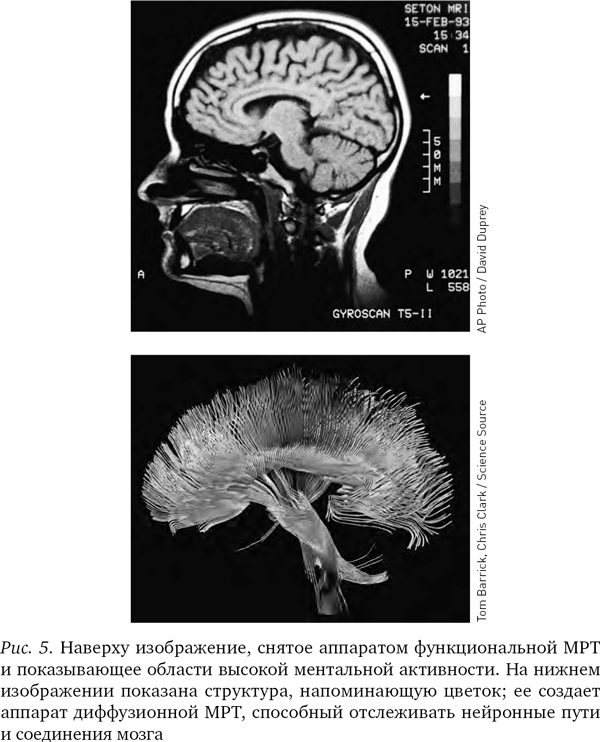

Вначале, когда аппараты МРТ только появились, они могли показывать структуру мозга лишь в статике и на различных его участках. Однако в середине 1990-х гг. был изобретен новый вид МРТ, получивший название функциональной магниторезонансной томографии, или фМРТ; и теперь аппараты уже различали присутствие кислорода в крови в сосудах мозга. (Иногда ученые обозначают маленькой буквой перед аббревиатурой МРТ тип аппарата, но мы будем использовать аббревиатуру МРТ во всех случаях.) На полученных при помощи МРТ изображениях не виден непосредственно ток электричества в нейронах, но поскольку без кислорода нейроны не получат энергии, насыщенная кислородом кровь косвенно указывает на поток электрической энергии в нейронах и наглядно показывает, как различные области мозга взаимодействуют между собой.

Различные химические элементы реагируют на разные частоты радиоволн по-разному, поэтому мы можем, изменяя частоту волны, определять, где какие элементы находятся. Как уже отмечалось, при фМРТ в основном отслеживаются атомы кислорода в крови и измеряют кровоток, но вообще-то аппарат МРТ можно настроить на любое вещество. В последнее десятилетие появилась новая разновидность МРТ – диффузионно-тензорная; она отслеживает движение воды в объеме мозга. Вода в мозге следует по нейронным путям, поэтому диффузионно-тензорная томография позволяет получить красивые картинки, напоминающие переплетение растущих в саду лиан. Теперь ученые могут мгновенно определить, как части мозга связаны между собой.